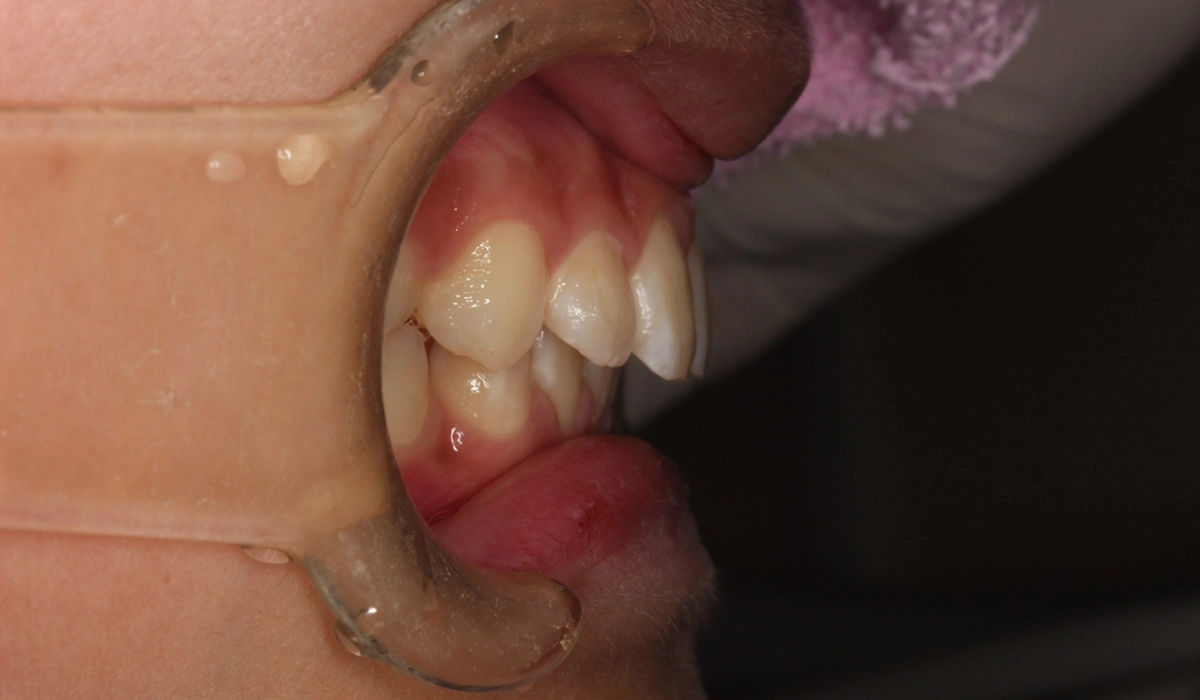

術前:右側

術後:右側